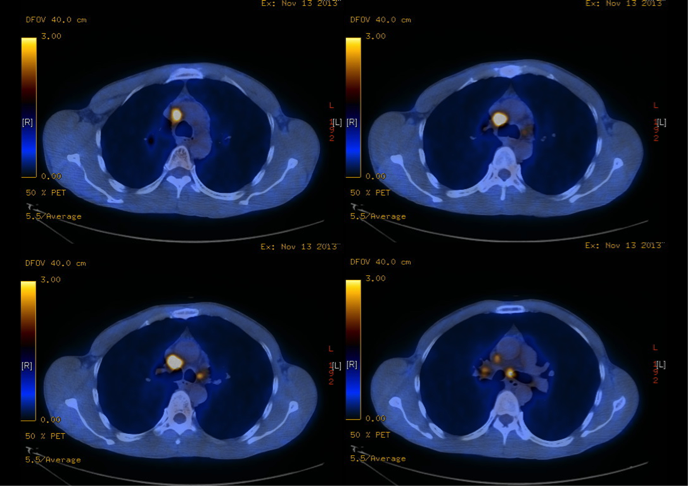

The patient was a chronic smoker (30 pack-years) and chronic drinker. He was a construction site worker and his past health was good. He presented with headache for a few weeks and was found to have signs of superior vena cava obstruction (SVCO). He did not have other complaint and the rest of the physical examination was normal. His CXR was unremarkable (Fig 4). His plain CT brain was also unremarkable. His initial blood tests including complete blood picture, renal & liver function test, erythrocyte sedimentation rate, urate, lactate dehydrogenase and tumor markers (including carcinoembryonic antigen, alpha-fetoprotein and prostate-specific antigen) were normal. His sputum was negative for culture, acid fast bacilli and cytology. His contrast CT thorax showed enlarged lymph nodes (LN) in the right lower paratracheal, pre-carinal & right hilar region and aorto-pulmonary window. The enlarged right lower paratracheal and precarinal LN compressed the brachiocephalic veins and superior vena cava (Fig 5). FOB with transbronchial needle aspiration under endobronchial ultrasound guidance (EBUS-TBNA) were done. The specimen of the right lower paratracheal LN was reported as suboptimal while the specimen from the right hilar LN was negative for any significant pathology. In view of SVCO was a potential medical emergency, we suggested surgical biopsy of the mediastinal LNs to ascertain their nature more definitively in order to guide subsequent management. He was then referred to the thoracic surgery clinic and PET-CT was done as suggested by the thoracic surgeon. The PET-CT was reported as “There were multiple enlarged hyper-metabolic mediastinal LNs (SUVmax 3.3-6.5) and the provisional diagnosis would include lymphoproliferative disease.” A hypermetabolic focus (1.7cm x 1.0cm x 2.3cm, SUVmax = 4.7) in the periphery of the right vastus lateralis muscle was also found incidentally (Fig 6A, 6B). At that juncture, the working diagnosis was SVCO due to possible lung carcinoma with LN metastases or lymphoma. The right thigh lesion could be part of the disease or something unrelated. Right anterior mediastinotomy and biopsy of the right lower paratracheal LN were done. Histology showed a piece of fibrous tissue with marked suppurative granulomatous inflammation. However, infective stains including Ziehl-Neelsen (ZN) stain were negative. His tuberculin skin test was 24mm (that was strongly positive) and his histoplasma antibody was negative. Standard anti-tuberculosis (TB) treatment was started and the signs of SVCO resolved progressively. Later, ultrasound guided FNA of his right thigh lesion showed granulomatous inflammation and one acid fast bacillus. Thus the final diagnosis was TB mediastinal lymphadenopathies causing SVCO, and right thigh TB infection. An interval CT about four months after anti-TB treatment showed the mediastinal LNs were decreased in size.

Figure 6a and 6b